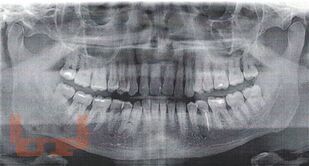

Эффективность трансдермальной системы гель «Поликатан» и «Тизоль» в комплексном лечении воспалительных заболеваний пародонта

В учебном пособии освещаются вопросы актуальности воспалительных заболеваний пародонта в стоматологии и социуме, аспекты этиологии и принципов лечения пародонтопатологий. Особое внимание уделяется применению геля «Поликатан» и «Тизоль» в комплексном лечении воспалительных заболеваний тканей пародонта.